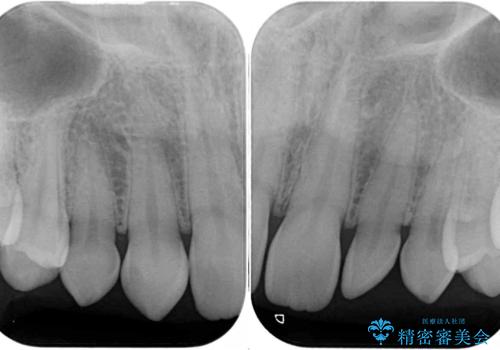

- 前歯の奇形や欠損、乳歯残存などによる審美障害を気にして来院された患者様です。

正中の隙間は矯正治療により閉じ、左右の4歯はオールセラミッククラウンにて補綴することとしました。